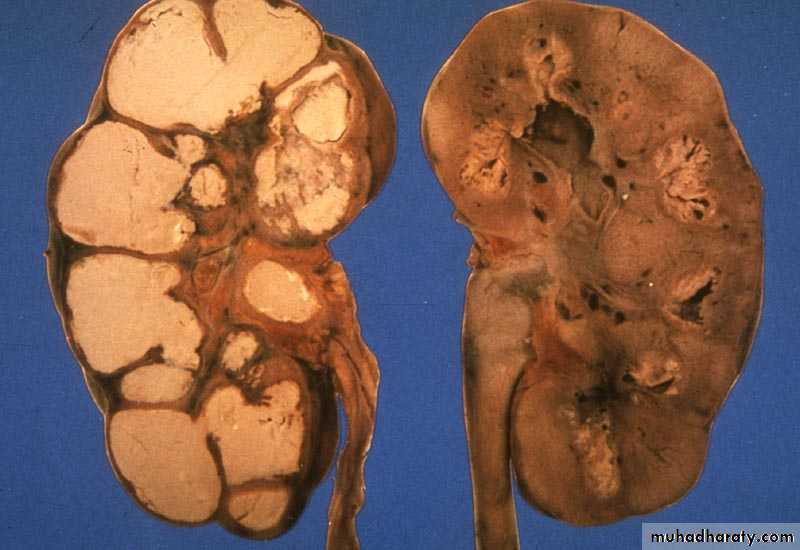

Renal TuberculosisBacteria: Mycobacterium TB

TB granuloma, caseation, open to the calyces.

Renal destruction, calcification.

RENAL TB